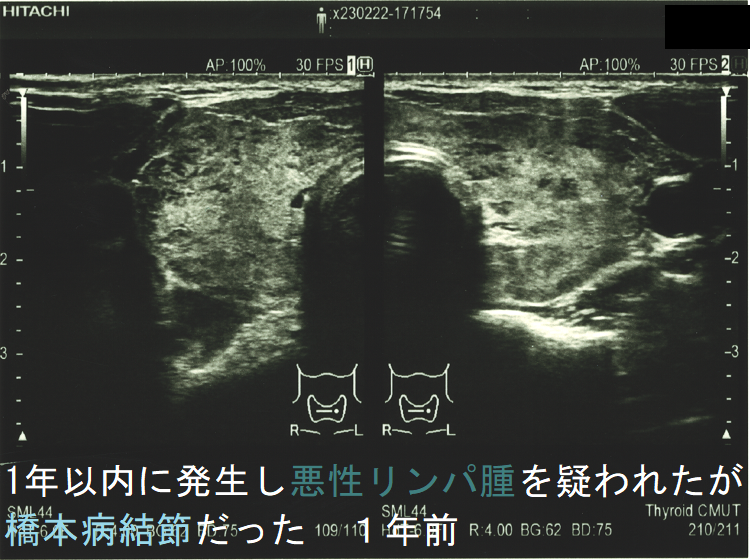

![1年以内に現れ悪性リンパ腫が疑われたが橋本病結節だった 1年前 (水平断)[拡大] 1年以内に現れ悪性リンパ腫が疑われたが橋本病結節だった 1年前 (水平断)[拡大]](../images/special/thyroid2/images20251130213537.png)